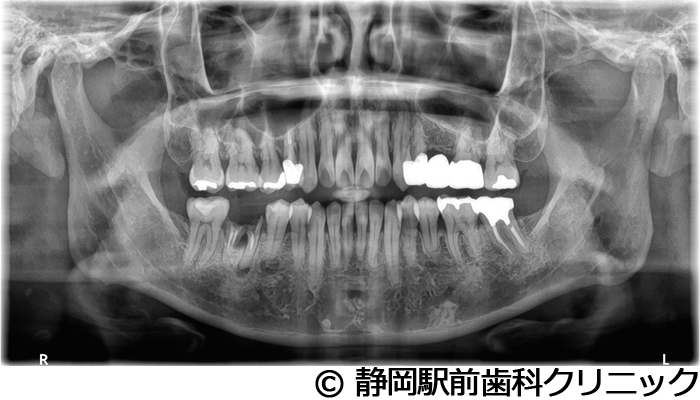

【症例3】右下インプラント埋入

- 治療前

- 治療後

- 治療名

- 右下インプラント埋入

- 費用

- 440,000円(税込)

- 期間

- 6ヵ月

治療内容

患者様の症状

右下の歯が折れてしまい、食べにくいため、インプラント治療希望。

治療方法

右下2本は抜歯を行い、骨の治癒後にCTを撮影し、詳細に治療計画を立案しました。その後、インプラントを埋入し、人工歯を被せて咬合の回復を行いました。

治療結果

患者様からは右でも好きな物を食べることができるようになり、喜んでいただきました。人工歯はセラミックにて作成し、見た目もご満足いただけました。

※治療結果は個人差があります。

治療を行う上での注意点(リスク・副作用)

術後は、出血、腫れ、痛みなどが出る可能性があります。